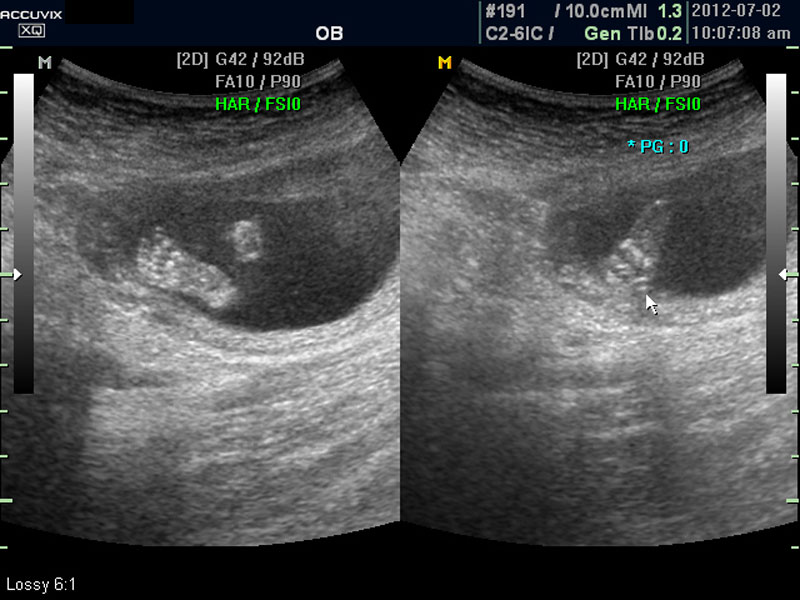

우선 초음파 사진에서 볼 것은 태아의 크기가 정상인가 하는 것입니다.

보통 태아의 발육은 머리부터 엉덩이까지의 크기인 CRL(Crown Rump Length의 약자)이 정상인가 하는 것과 태아의 두상 크기인 BPD(BiParietal Diameter의 약자)가 정상 범위에 들어 있는가 하는 것으로 판단합니다.

화면에서 좌측이 태아 머리 부분으로 빨간 펜으로 표시되어 있습니다.

초음파 상 태아의 머리가 좌측인가 우측인가 하는 것은 초음파 탐촉자의 위치를 어디에 두었느냐에 따라 다른 것 뿐으로 화면상 어디 위치하는 지는 중요하지 않습니다.

태아의 머리가 정상 모양인가 크기는 정상인가 하는 것을 살펴 본 후에는 태아의 크기를 측정하고 가슴, 복부, 엉덩이 부분, 상하지 부분이 정상인가 하는 것을 살펴 봅니다.

위 사진에서 빨간 동그라미로 표시한 부분이 태아의 머리를 위에서 내려다 본 수평 단면입니다.

하얗게 보이는 것은 뼈이고 내부에 검게 보이는 것은 뇌실에 고인 척수액 부분이며 내부의 하얀 부분은 뇌조직과 뇌실 내 맥락막이라고 하는 것입니다.

화면에서는 위쪽에 하얗게 균일하게 보이는 것이 태반의 모습입니다.

사진에서 검게 보이는 것이 양수입니다. 양수에 대하여는 색깔이나 밀도 등 다른 요소는 알기 어려워서 그 양만 가지고 판단을 하게 됩니다.